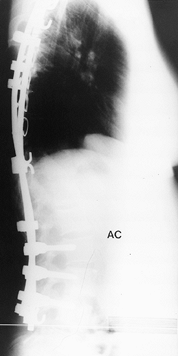

as for the type II to IV curve patterns. (Fig. 156.25, Fig. 156.26, Fig. 156.27, Fig. 156.28, Fig. 156.29 and Fig. 156.30 show typical cases.)

![]() |

|

Figure 156.25. Preoperative AP radiograph of the right thoracic curve.

Figure 156.26. Postoperative AP radiograph of the right thoracic curve.

Figure 156.27. Postoperative lateral radiograph of the right thoracic curve.

Figure 156.28. Preoperative AP radiograph of type I thoracic and lumbar curves.

Figure 156.29. Postoperative lateral radiograph of type I thoracic and lumbar curves.

Figure 156.30. Postoperative AP radiograph of type I thoracic and lumbar curves.s